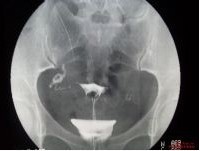

得了盆腔积液很严重吗?盆腔积液分生理性和病理性两种,生理性的积液可自行消失不必治疗,病理性的盆腔积液要是没有得到及时有效的解决,那么就可能给患者带来一些比较严重的后果。

罗女士较近频繁出现低烧的情况,并且很容易觉得累,没什么精神。原以为是工作劳累导致,但是之后出现的较为严重的腹痛让她到做了检查,发现所有的不舒服都是因为得了盆腔积液引起的,并且平时的失眠、白带异常等情况也和这种疾病有关!

黄女士出现带下量多、下腹疼痛的情况已经有较长时间了。原以为忍一忍就能过去,没想到腹痛越来越严重,月经也出现了异常情况,只好到金华妇科医院接受检查,发现是得了盆腔积液,并且还出现了输卵管堵塞的情况。

高女士是是因为月经量异常增多,并且痛经和腹痛比较严重到金华妇科医院就诊的,而就诊时已经距离该患者出现症状间隔大半年了。检查结果显示高女士得了盆腔积液,并且因为积液的存在造成了盆腔淤血,卵巢和输卵管也出现了粘连的情况。

以上是金华妇科医院妇科门诊的一些盆腔积液临床案例,可以发现该疾病出现后对女性患者可造成的影响是非常大的。不管是日常生活还是身体健康还是生育能力,都可因盆腔积液而受到影响。